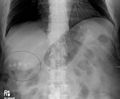

Gallstones typically form in the gallbladder and may result in symptoms if they block the biliary system.

A gallstone is a stone formed within the gallbladder out of bile components.[2] The term cholelithiasis may refer to the presence of gallstones or to any disease caused by gallstones.[5] Most people with gallstones (about 80%) never have symptoms.[2][3] However, if a gallstone blocks the bile duct, a cramp-like pain in the right upper part of the abdomen, known as biliary colic (gallbladder attack) can result.[4] This happens in 1–4% of those with gallstones each year.[4] Complications of gallstones may include inflammation of the gallbladder (cholecystitis), inflammation of the pancreas (pancreatitis), jaundice, and infection of a bile duct (cholangitis).[4][6] Symptoms of these complications may include pain of more than five hours duration, fever, yellowish skin, vomiting, dark urine, and pale stools.[2]

Risk factors for gallstones include birth control pills, pregnancy, a family history of gallstones, obesity, diabetes, liver disease, or rapid weight loss.[2] The bile components that form gallstones include cholesterol, bile salts, and bilirubin.[2] Gallstones formed mainly from cholesterol are termed cholesterol stones, and those mainly from bilirubin are termed pigment stones.[2][3] Gallstones may be suspected based on symptoms.[4] Diagnosis is then typically confirmed by ultrasound.[2] Complications may be detected on blood tests.[2]